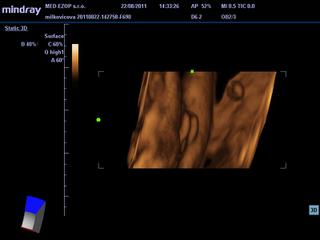

Mne prvý syn podľa tohto vyšiel, ale teraz mi zas vychádza chlapec...no na usg 4:1 vraj dievčatko...čo myslíte? Má niektorá podobné foto z usg? Chlapček, či dievča? 😲